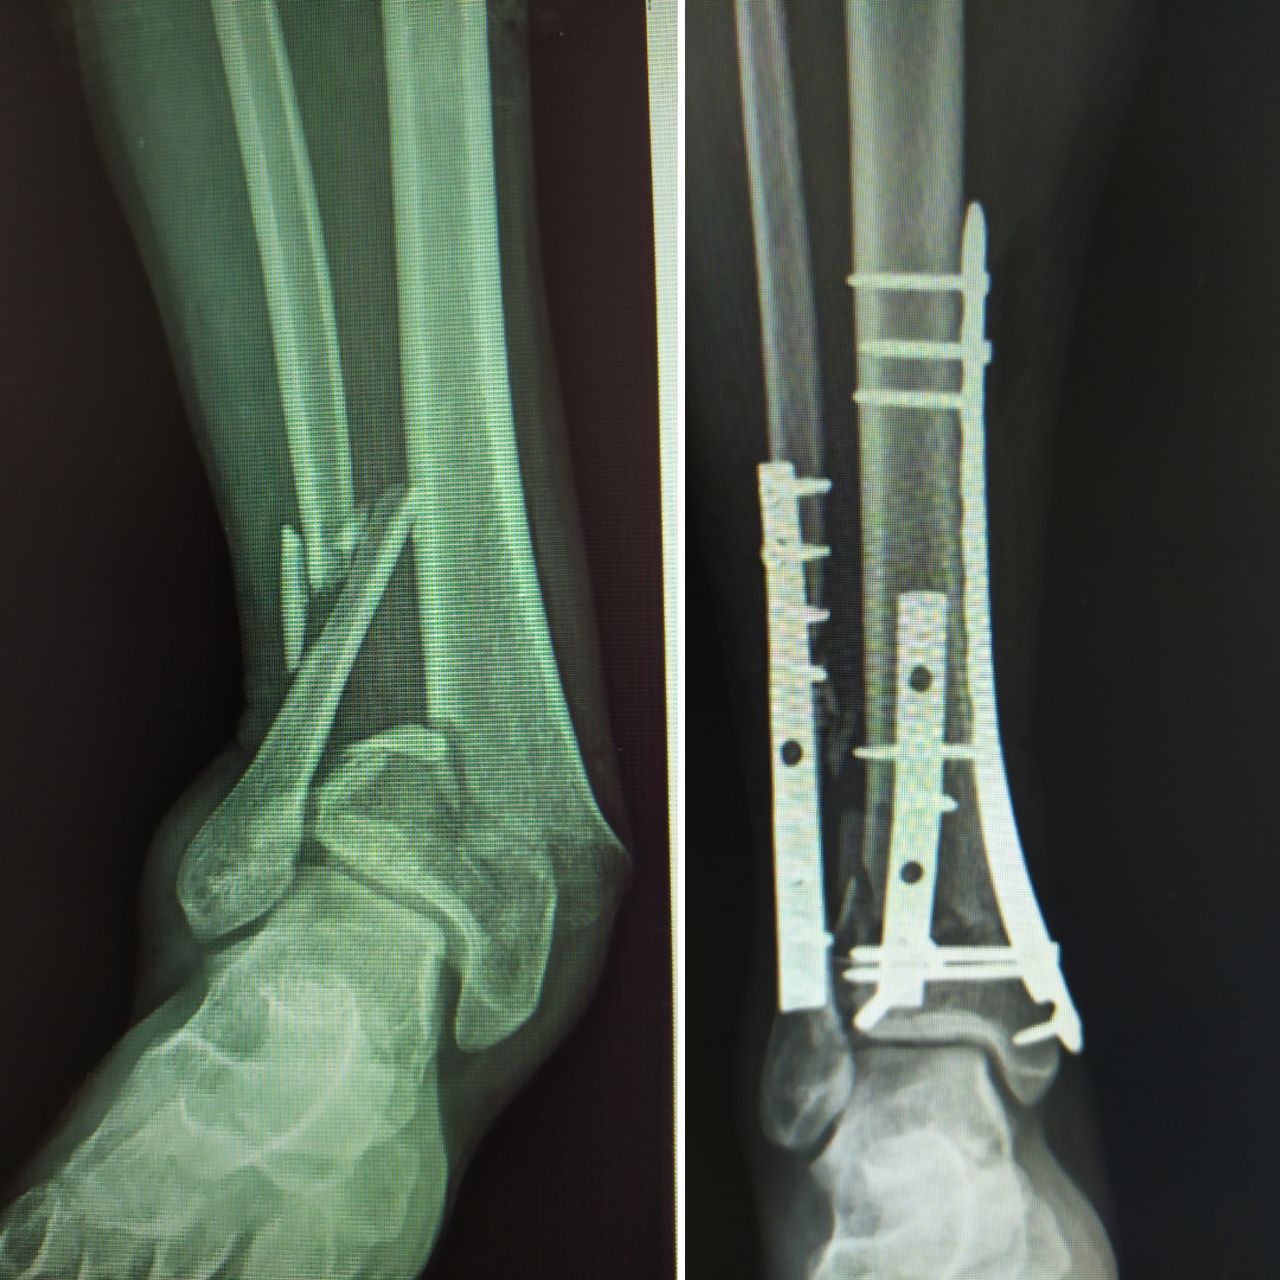

Querido paciente, soy Traumatólogo y Ortopedista egresado del Hospital Central de la Universidad Autónoma de San Luis Potosí, donde me especialicé a tratar todo tipo de problemas en el sistema musculoesqueletico, desgaste, fracturas, luxaciones, lesiones ligamentarias de (hombro, codo, mano, muñeca, columna, cadera, rodilla, pie y tobillo)

Posteriormente hice una Alta Especialidad en el Hospital de la Cruz Roja Mexicana de Mérida Yucatán, donde aprendí a tratar patología específica y compleja de pie y tobillo ( desgaste de tobillo, espolón Calcaneo y Fascitis plantar, Hallux Valgus (Juanetes), Pie plano del niño y del adulto, pie cavo, deformidades de los dedos menores del pie, pie diabético, artropatía de charcot, lesiones del tendón de Aquiles, lesiones deportivas.

Tuve la oportunidad de estar en "Centre Hospitalier de Dax - Côte d'Argent" en FRANCIA, donde aprendí a utilizar los mejores y más novedosos materiales para tratar todo lo relacionado a fracturas, columna y artroscopia.